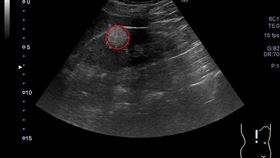

獨/女星「右腎長4公分瘤」!醫曝危險度

42歲女星王嫚萱長期在生理期間,側腰感覺劇烈痠痛,就...

女星腎臟長腫瘤開刀!醫籲這類女性要小心

41歲女星王嫚萱(舊名王湘瑩)2022年改名後積極復...

健檢發現腎臟長腫瘤超怕 醫吐這句話

台中45歲李女士日前健檢發現右腎有一顆2公分腫瘤,令...